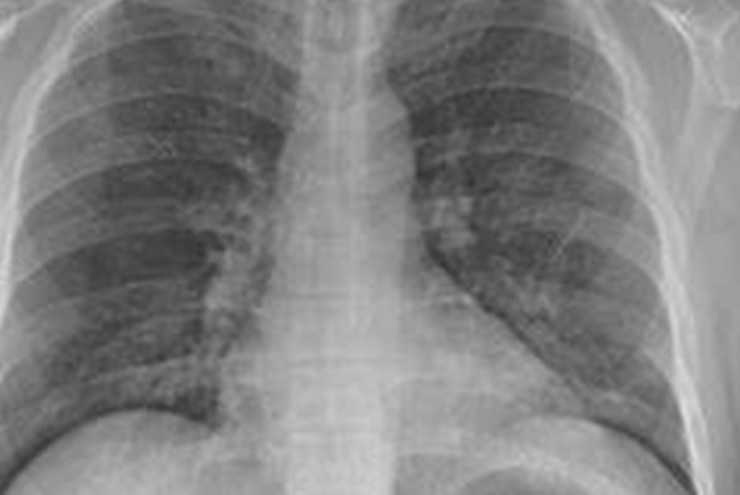

Cúm B cũng có thể gây biến chứng nặng như viêm phổi do virus cúm hoặc bội nhiễm vi khuẩn.

Cúm là bệnh nhiễm trùng đường hô hấp cấp tính do vi rút, có khả năng lây nhiễm cao và lây lan rất nhanh trong cộng đồng.